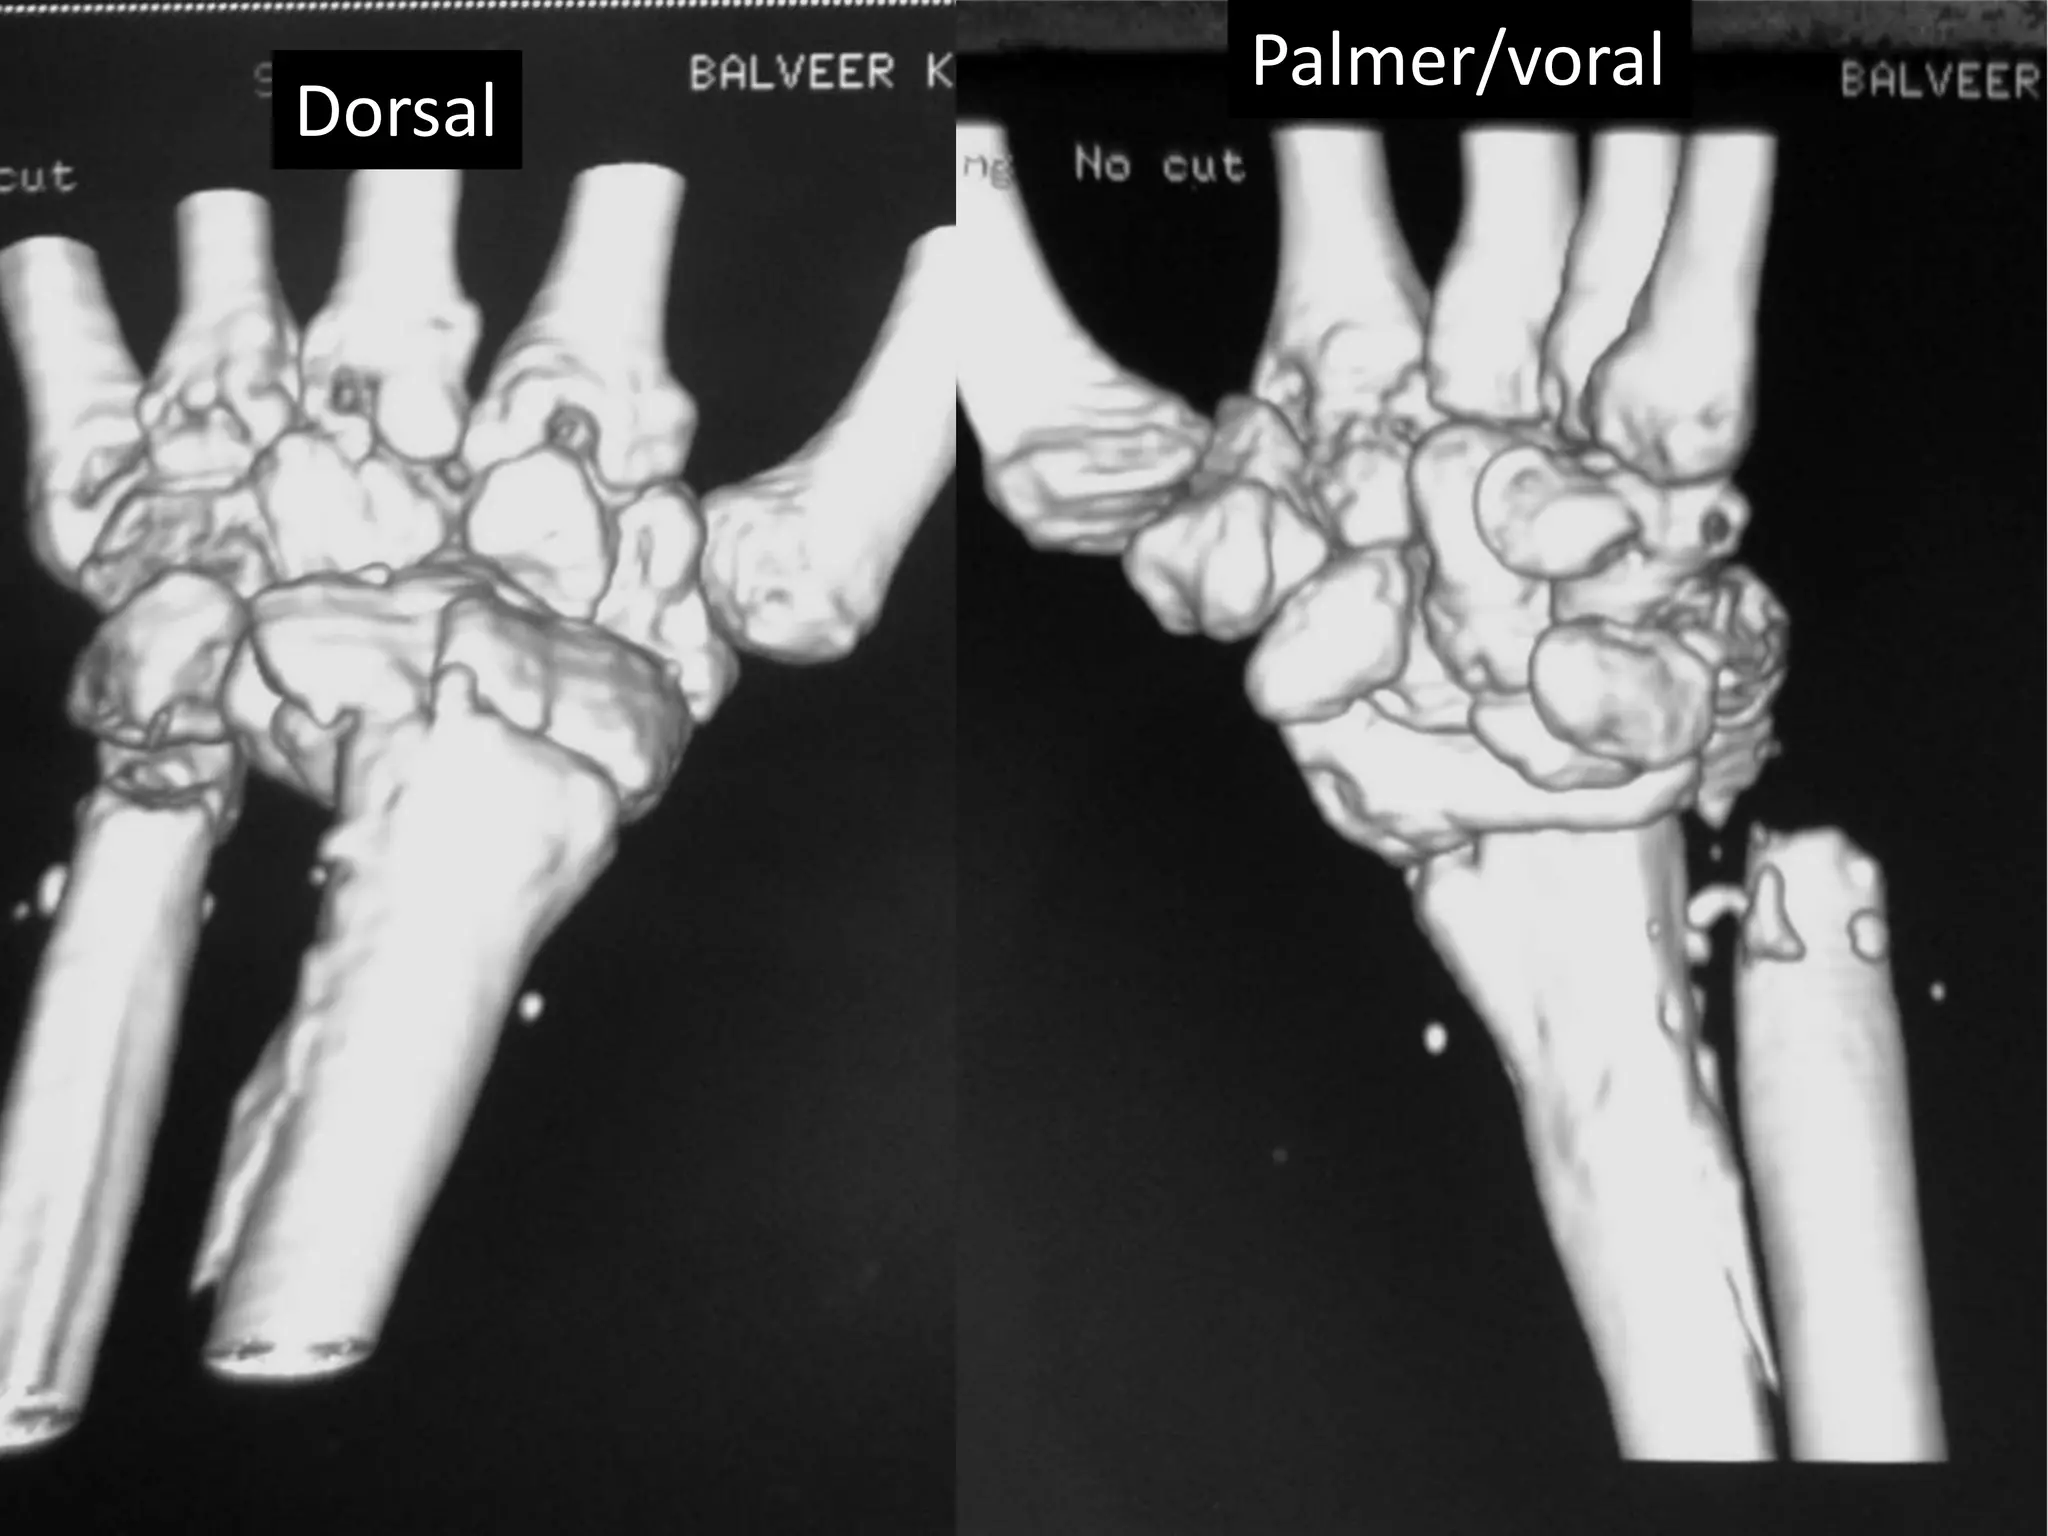

Severe Palmer flexion and ulnar deviation deformity

Dorsal

Palmer/voral

Ulnar Radial

Palmer surface

Severe Palmer flexionand ulnar deviation deformity